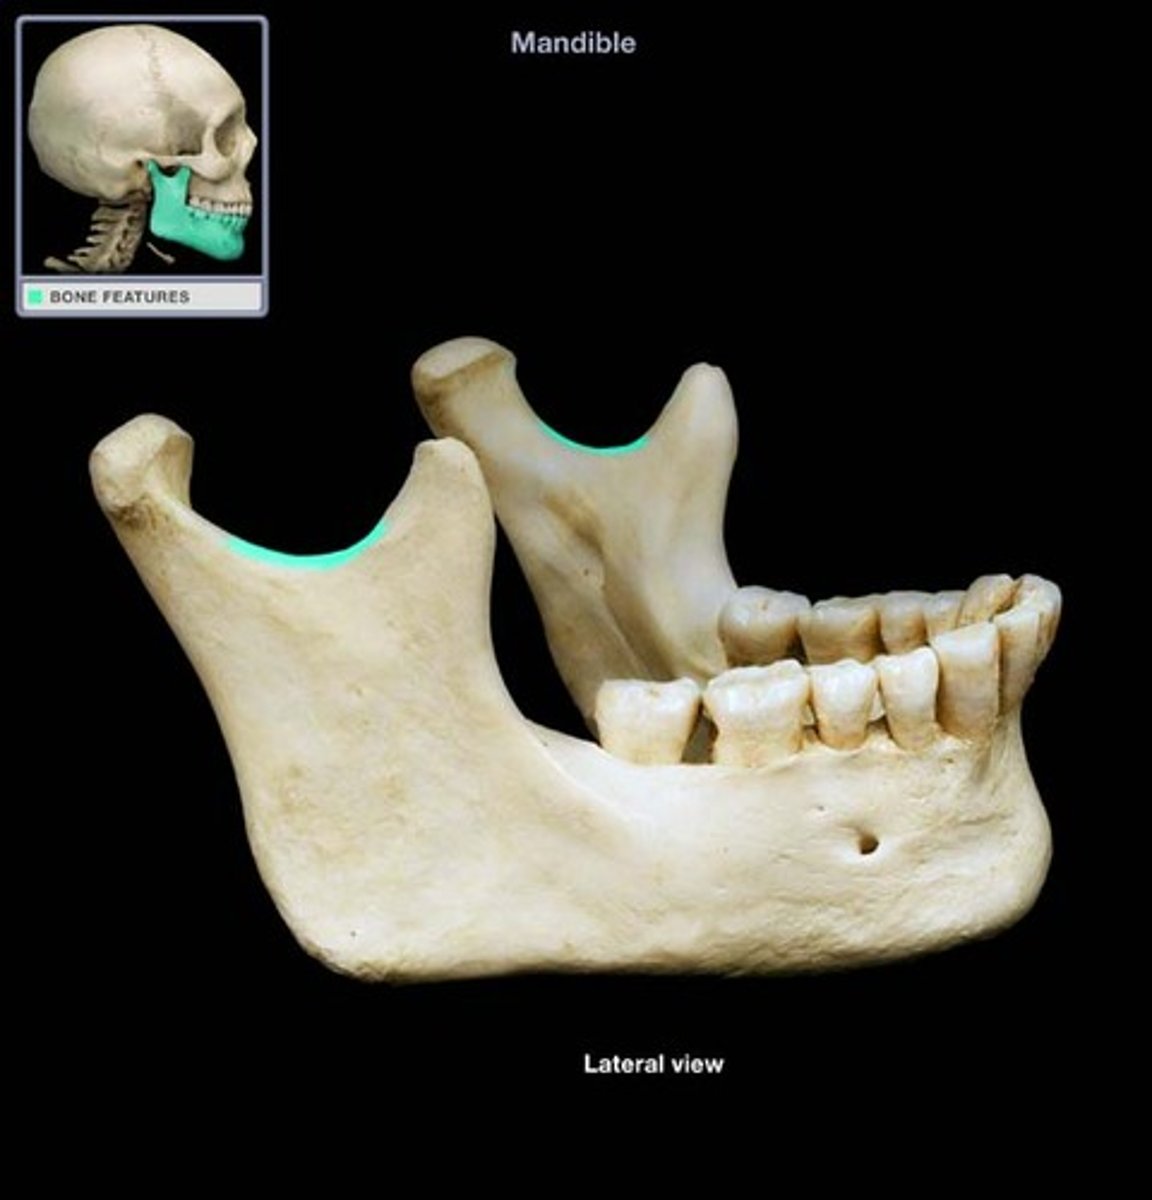

Mandibular notch

- between coronoid process and condyloid process

- forms lower part of Y

what is this